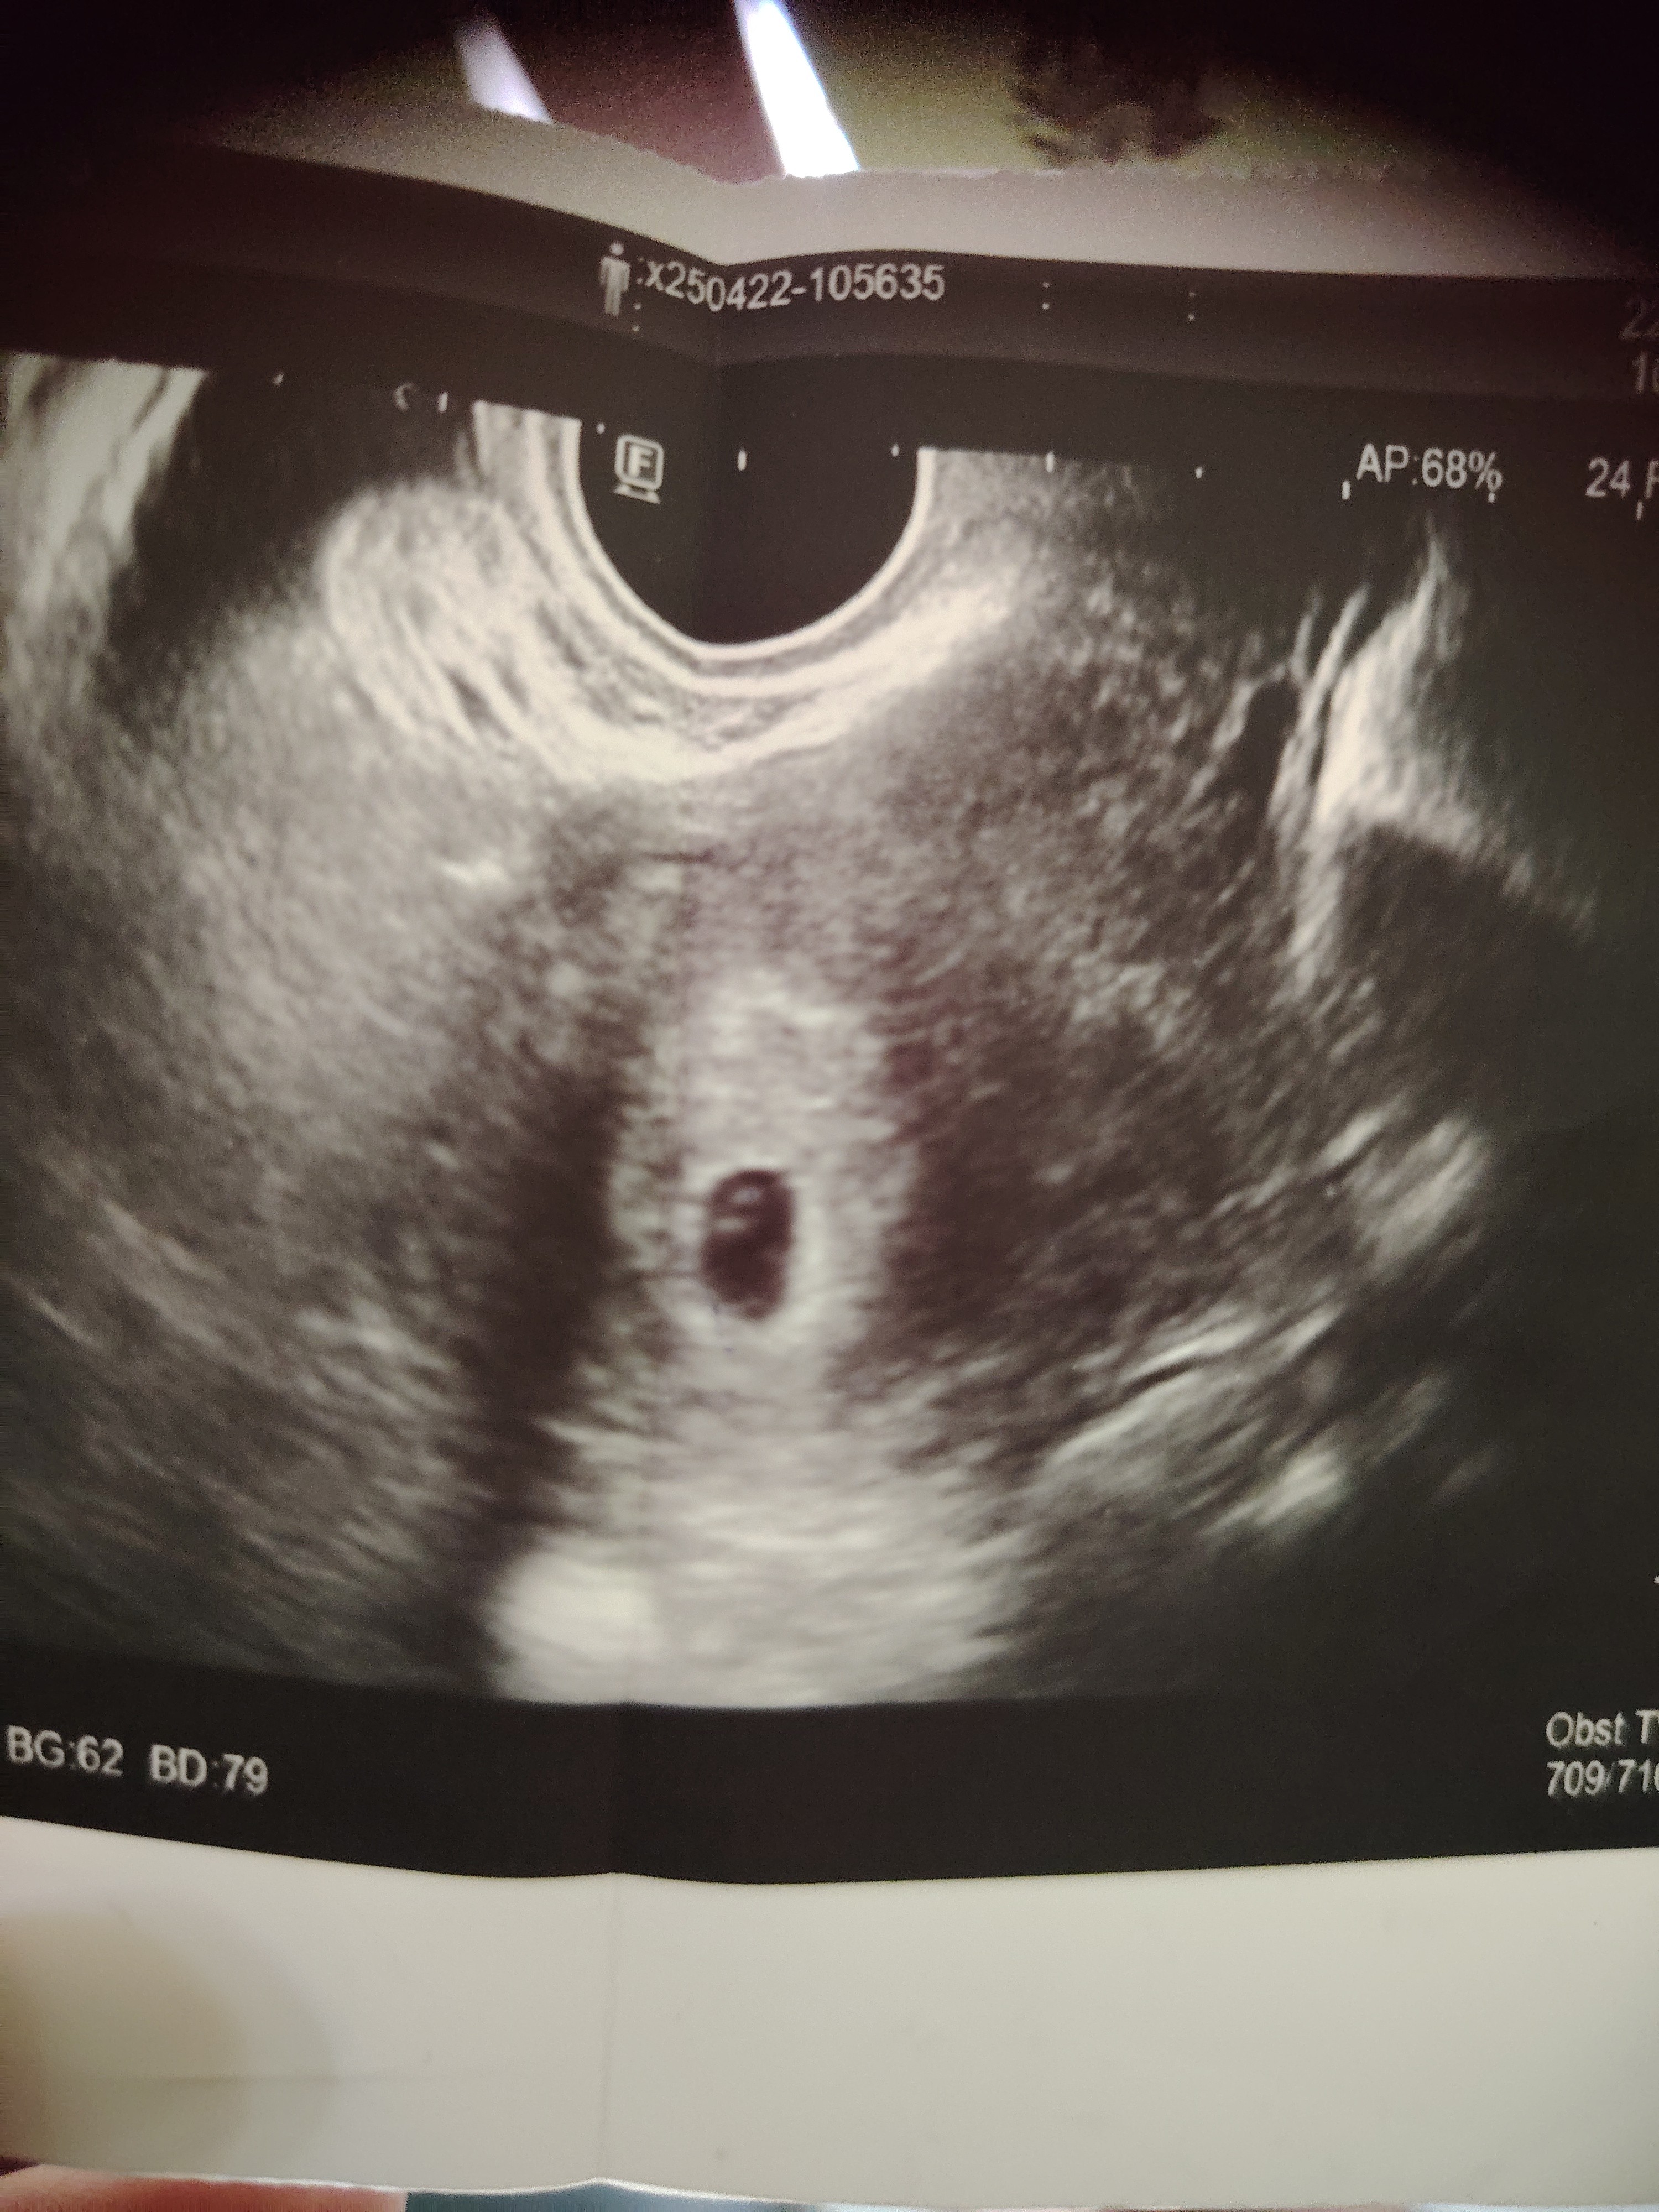

To właśnie moje usg, ale lekarz kazał przyjść za 2 tygodnie bo pęcherzyk jest ale zarodka według niego jeszcze nie widać. Jutro zrobię z rana Bete a w czwartek idę prywatnie, a pytanie co według was te 2 kropki na usg w pęcherzyk ( taka stara a się nie znam) 😁 czyżby to pęcherzyk żółciowy ale dlaczego dwie kropeczki

Koleżanko to jest pęcherzyk żółtkowy . Zmień to bo zaraz zlecą się i że źle napisałaś.

wg mnie to pęcherzyk żółtkowy tylko lekarz go tak ujął na usg, pewnie nie szło go w całości pokazać. Teraz czekanie aż na pęcherzyku pojawi się zarodek z sercem - tzw brylancik